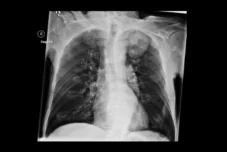

При обнаружении признаков рака легкого на рентгенологическом снимке или КТ онколог в течение одного рабочего дня должен организовать проведение биопсии. Во время процедуры врач забирает небольшую часть новообразования для исследования.